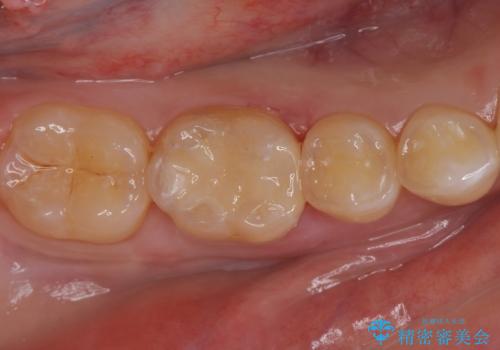

奥歯が欠けた セラミックインレーでの修復後、ナイトガード装着